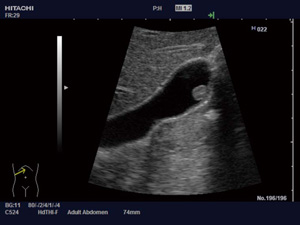

1.HdTHI(High definition dynamic Tissue Harmonic Imaging)

ハーモニック信号を広帯域化し,これまでほとんど利用できなかった低周波結合波をプローブ帯域内にシフトし,画像化した(図1,2)。これにより,従来のdTHIよりさらに空間分解能と深部感度の向上が図られている。

図1 HdTHI ON |

図2 HdTHI |